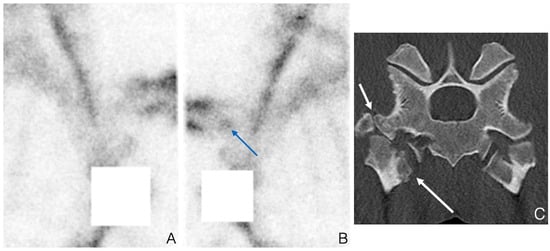

3.1. Imaging of Vertebral Column, Ribs and Proximal Limbs

3.2. Scintigraphy Combined with CT and MRI